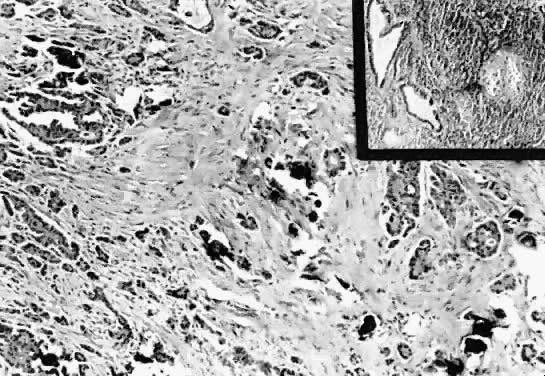

The histologic criteria for the diagnosis are as follows (Figs. 13 to 15):

Fig. 13. Serous psammocarcinoma of the ovary. The section shows numerous psammoma bodies in the stroma, cyst lumen, and papillae (hematoxylin and eosin, 85).

Fig. 14. Photomicrograph of a psammocarcinoma to illustrate psammoma bodies in the papillary component of the tumor. Atypical cuboidal epithelial cells with prominent nucleoli line the papillae (200).

Fig. 15. Serous psammocarcinoma. The epithelial component diffusely infiltrates the desmoplastic stroma. Few psammoma bodies are present (hematoxylin and eosin, 212). Inset. Section of a periaortic lymph node involved by tumor. Observe the atypical glandular epithelium. The glands in the center exhibit atypical papillary structures (hematoxylin and eosin, 212).

1. Destructive invasion of the stroma, vascular invasion, or, in extraovarian tumors, invasion of intraperitoneal viscera

2. Mild to moderate cytologic atypia

3. Occasional nests of solid areas of epithelial proliferation no more than 15 cells in diameter

4. At least 75% of papillae and nests associated with or completely replaced by psammoma body formation